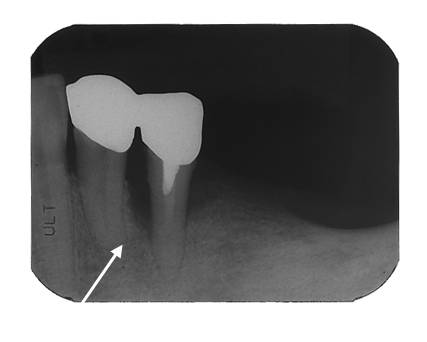

歯周組織再生療法後

治療前のレントゲンでは、矢印で指している部位の骨が溶けてしまっており黒く写っていますが、歯周組織再生療法後は、黒い部分が白く写っており、骨が再生しているのが認められます。歯肉の炎症も改善しました。